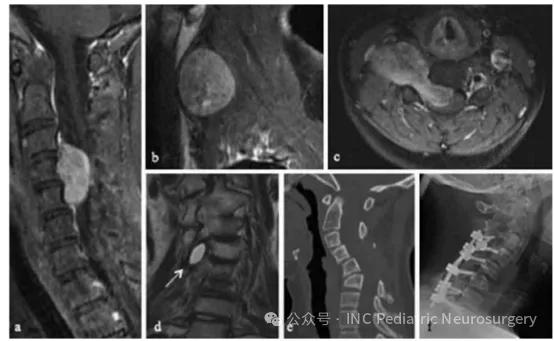

于2013年就诊,11岁,主诉为颈部和手臂疼痛持续2周。MRI检查显示C1-C3节段大体积侵袭性脊索瘤,伴有明显的右侧外向延伸(图2)。患者在外院接受C3-C5椎板切除术,但因术中体感诱发电位(SSEP)信号丢失,肿瘤切除不完全且手术被迫中止。

转入SickKids儿童医院后,患者接受经右前外侧颈部入路的肿瘤切除术,实现肿瘤全切(gross total resection)。病理诊断为经典型脊索瘤,免疫组化结果显示S100、广谱细胞角蛋白(pan-CK)、CK-19、CK-8、癌胚抗原(CEA)、低分子量细胞角蛋白(LMW-K)、波形蛋白(vimentin)以及EMA均为阳性。

术后随访影像显示右侧存在少量囊性残留病灶,经70Gy光子放疗后得到良好控制。手术及放疗两年后,患者出现颈椎后凸侧弯(cervical kyphoscoliosis)伴颈部疼痛,随后接受C3-T1节段内固定融合术。

图2. 患者2 C3-C5脊索瘤影像资料

(a)术前矢状位T1加权增强MRI;

(b)术前轴位T1加权增强MRI;

(c)术前矢状位CT;

(d)术后矢状位T1加权增强MRI,显示右侧囊性残留;

(e)术后2年矢状位CT,可见进行性颈椎后凸侧弯(kyphoscoliosis);

(f)术后C3-T1内固定融合侧位X线片。